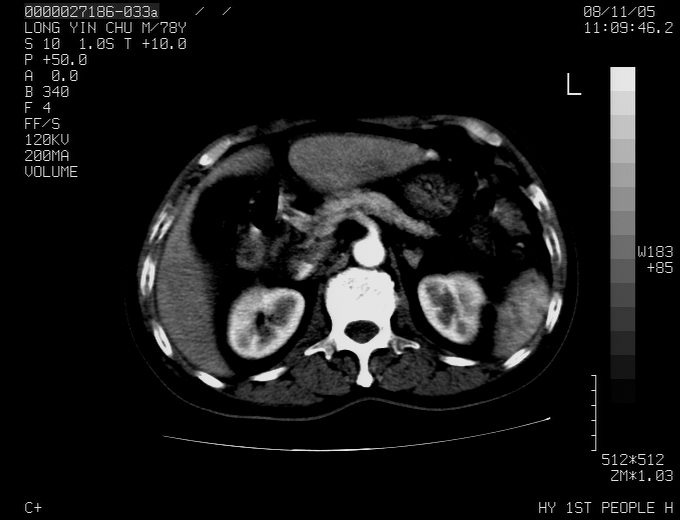

腹胀,腹痛就诊,男性,78岁,外院b超未见异常。

肝ca,脾肾转移

支持脾肾转移瘤,双侧胸腔积液。

考虑弥漫性肝癌并脾及双肾转移.双侧胸水.

图片质量欠佳:多考虑:左侧肾癌。脾脏转移!胸膜转移!

肝脾肾转移瘤可能性大,左肾不除外梗塞,双侧胸水

考虑肝癌并双肾及脾脏转移;双侧胸腔积液。